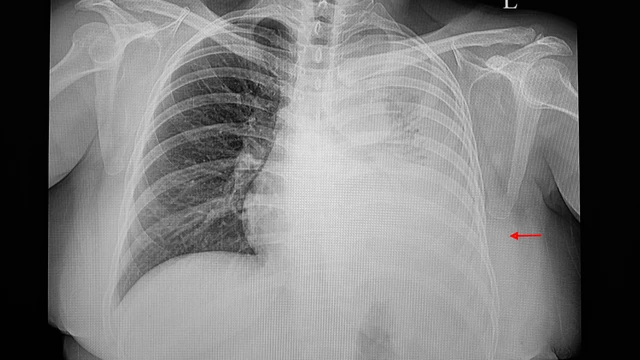

Tràn dịch màng phổi là một triệu chứng rất thường gặp với tỷ lệ mắc là như nhau ở cả nam và nữ. Tràn dịch màng phổi thường là do ảnh hưởng từ bệnh lý khác gây nên. Do vậy, khi có dấu hiệu của tràn dịch màng phổi, hãy liên hệ bác sĩ ngay để kịp thời can thiệp và có phương pháp điều trị phù hợp.